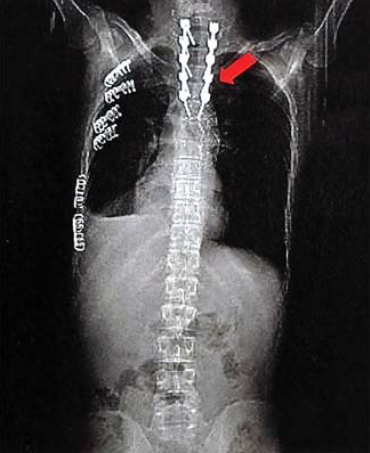

1. ábra.

Autóbalesetben sérült 26 éves ffi. DSA felvétele 3 héttel a baleset után. Az isthmicus szakaszon álaneurysma ábrázolódott.

1. 26 éves ffi autóbalesetben utasként szenvedett el mellkasi zúzódást, bordarepedést és tüdő contusiót. A kiszélesedett mediastinum és kis mennyiségű mellkasi folyadékgyülem vetette fel isthmicus tompa aortasérülés lehetőségét, amit DSA vizsgálattal igazoltunk. Hypotenziv kezelés mellett keringése stabil, a mediastinum kiszélesedése és haematologiai statusa nem változott. 3 héttel a sérülést követően bal oldali thoracotomia útján aorto-aorticus Dacron grafttal, mesterséges keringés alkalmazása nélkül, interpositiot végeztünk (1.,2.,3. ábra).